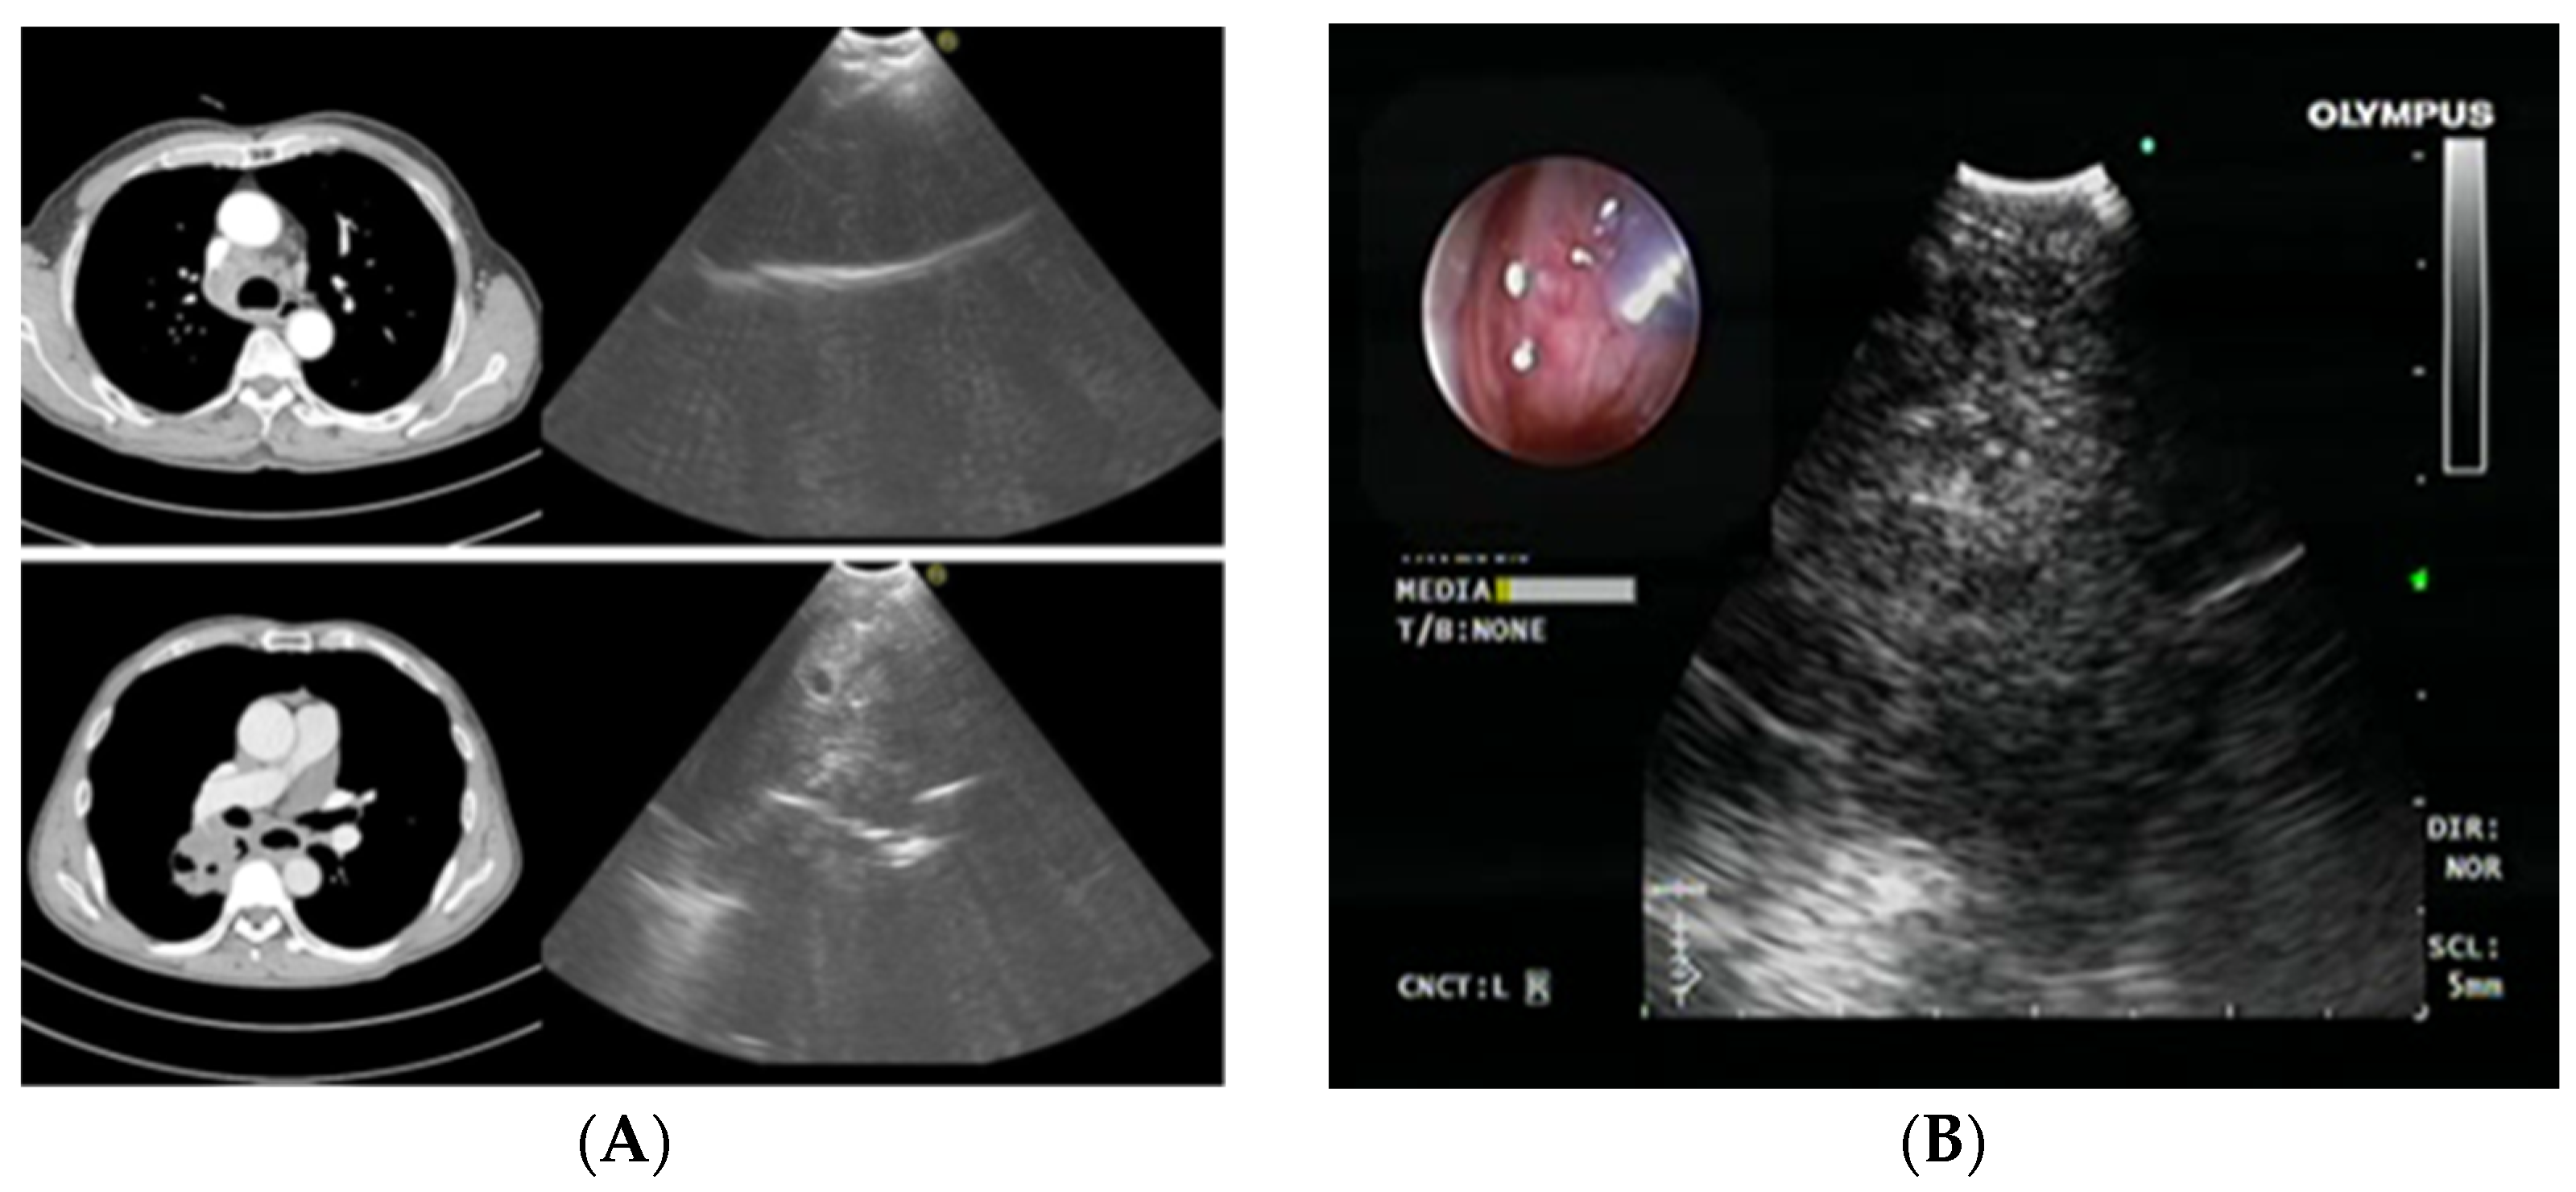

2.3. Endobronchial Ultrasound (EBUS) Transbronchial Needle Aspiration

- Wahidi, M.M.; Herth, F.; Yasufuku, K.; Shepherd, R.W.; Yarmus, L.; Chawla, M.; Lamb, C.; Casey, K.R.; Patel, S.; Silvestri, G.A.; et al. Technical aspects of endobronchial ultrasound-guided transbronchial needle aspiration CHEST guideline and expert panel report. Chest 2016, 149, 816–835. [Google Scholar] [CrossRef]

- Labarca, G.; Folch, E.; Jantz, M.; Mehta, H.J.; Majid, A.; Fernandez-Bussy, S. Adequacy of Samples Obtained by Endobronchial Ultrasound with Transbronchial Needle Aspiration for Molecular Analysis in Patients with Non-Small Cell Lung Cancer. Systematic Review and Meta-Analysis. Ann. Am. Thorac. Soc. 2018, 15, 1205–1216. [Google Scholar] [CrossRef]

- Trisolini, R.; Cancellieri, A.; Tinelli, C.; De Biase, D.; Valentini, I.; Casadei, G.; Paioli, D.; Ferrari, F.; Gordini, G.; Patelli, M.; et al. Randomized trial of endobronchial ultrasound-guided transbronchial needle aspiration with and without rapid on-site evaluation for lung cancer genotyping. Chest 2015, 148, 1430–1437. [Google Scholar] [CrossRef]

- Dooms, C.; Vander Borght, S.; Yserbyt, J.; Testelmans, D.; Wauters, E.; Nackaerts, K.; Vansteenkiste, J.; Verbeken, E.; Weynand, B. A randomized clinical trial of flex 19G needles versus 22G needles for endobronchial ultrasonography in suspected lung cancer. Respiration 2018, 96, 275–282. [Google Scholar] [CrossRef]

- Garrison, G.; Leclair, T.; Balla, A.; Wagner, S.; Butnor, K.; Anderson, S.R.; Kinsey, C.M. Use of an Additional 19-GEBUS-TBNANeedle Increases the Diagnostic Yield of EBUS-TBNA. J. Bronchol. Interv. Pulmonol. 2018, 25, 269–273. [Google Scholar] [CrossRef]